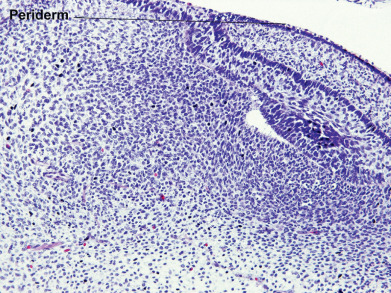

During the first weeks of life, the fetus is covered by a layer of nonkeratinizing cuboidal cells called the periderm ( Fig. 1.2 ). Later, the periderm is replaced by a multilayered epidermis. Adnexal structures, particularly follicles and eccrine sweat units, originate during the third month of fetal life as downgrowths from the developing epidermis. Later, apocrine sweat units develop from the upper portion of the follicular epithelium and sebaceous glands from the midregion of the follicle. Adnexal structures appear first in the cephalic portion of the fetus and later in the caudal portions.